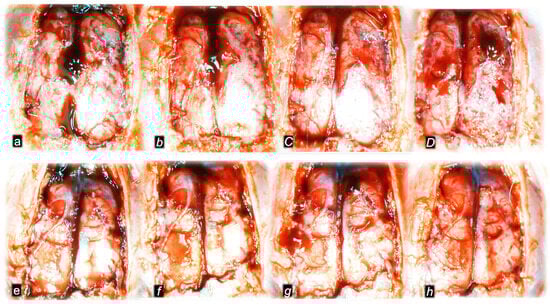

Without therapy, post-embolization syndrome occurs with vessel congestion (superior mesenteric vein and inferior caval vein, due to the trapped volume, congested liver and lung), dilated heart, and collapsed vessels (not-functioning azygos vein) and swollen brain) (Figure 3, Figure 4 and Figure 5).

Figure 5.

Illustrative presentation of brain (swelling) (a,B,c,D,e,F) and heart (dilatation) (g,H,i,J,k,L) in rats that in rats that received 0.1 mL of sodium laurate (10 mg/kg) into the inferior caval vein, and then saline (control, small italic letters) or BPC 157 therapy (capital italic letters). Presentation immediately after sacrifice (brain) or immediately before sacrifice (heart) at 15 min (a,B,g,H), 30 min (c,D,i,J) and 60 min (e,F,k,L) following application of 0.1 mL of sodium laurate (10 mg/kg) into the inferior caval vein.

Without therapy, all of the laurate-injected rats converged to similar effects of continuous vascular failure, and recovery was not able to be spontaneously activated (Figure 3 and Figure 4). The failed collateral pathways presented in each of the given time points failed throughout the complete experimental period. Contrarily, advanced collateral pathways presentation consistently occurred with BPC 157 therapy (either intraperitoneal or intragastric) (Figure 3 and Figure 4). The particular vessel recruitment as a resolution for major vessel failure and stasis counteraction, peripherally and centrally, accords with blood pressure disturbances being attenuated/eliminated, and thrombosis being almost annihilated in veins and arteries, peripherally and centrally (Table 1). Thus, after laurate inferior caval vein embolization, BPC 157 therapy may fully reverse post-embolization syndrome.

Consequently, the particular effects of BPC 157 on the relative volume (Table 2) illustrate the activated defensive response as an immediate therapy effect. There was a reversal of the failed volume. Presentation of azygos vein collapse (as well as the abdominal aorta) was reversed and the azygos vein was reactivated (Figure 3). Likewise, there was a reversal of the increased relative volume (i.e., the superior mesenteric vein and inferior caval vein congestion, which BPC 157 might decrease) (Table 2, Figure 4).

As an immediate therapeutic effect, this could be illustrated by gross presentation in Figure 3, Figure 4 and Figure 5.

The essential point of the therapy was to reactivate the azygos vein, and, thereby, the collapsed volume of the azygos vein (as well as the abdominal aorta) was reversed (i.e., volume increased as the azygos vein was reactivated, thereby enabling direct blood delivery to occur) (Figure 3).

Likewise, we posit that this rescuing response results in the counteraction of the increased relative volume of the superior mesenteric vein and inferior caval vein (congestion), which were counteracted and reversed to normal vessel presentation (Figure 4).

The consistent outcome is that the presentation of these vessels (Figure 3 and Figure 4) and the heart (Figure 5) returns to close to normal vessel and heart presentation and close to normal functioning to re-establish blood flow (multiorgan lesions are largely attenuated) due to BPC 157 therapy. As further support, BPC 157 therapy induced a considerable change toward normal brain presentation and negative pressure values (Table 1 and Table 2) (i.e., brain swelling occurred with the increased intracranial (superior sagittal sinus) hypertension and increased volume (associated with considerable brain injuries) due to the laurate injection, which was reversed by BPC 157 (Figure 5).